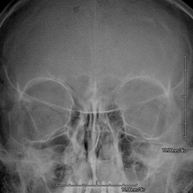

- RX Senos Paranasales

Técnica mediante la cual, utilizando rayos X, se obtienen imágenes de los senos paranasales para su estudio. Indicaciones: dificultad respiratoria nasal, tos crónica, cefalea, mucosidad.

- RX Orbitas

Técnica mediante la cual, utilizando rayos X, se obtienen imágenes de las órbitas para su estudio. Indicaciones: cuerpo extraño ocular, traumatismo, infecciones.